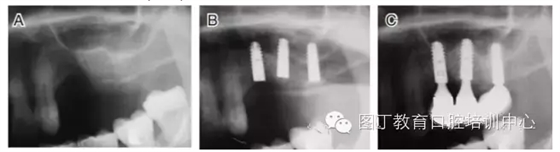

病例5 多顆種植體(圖7)

圖7